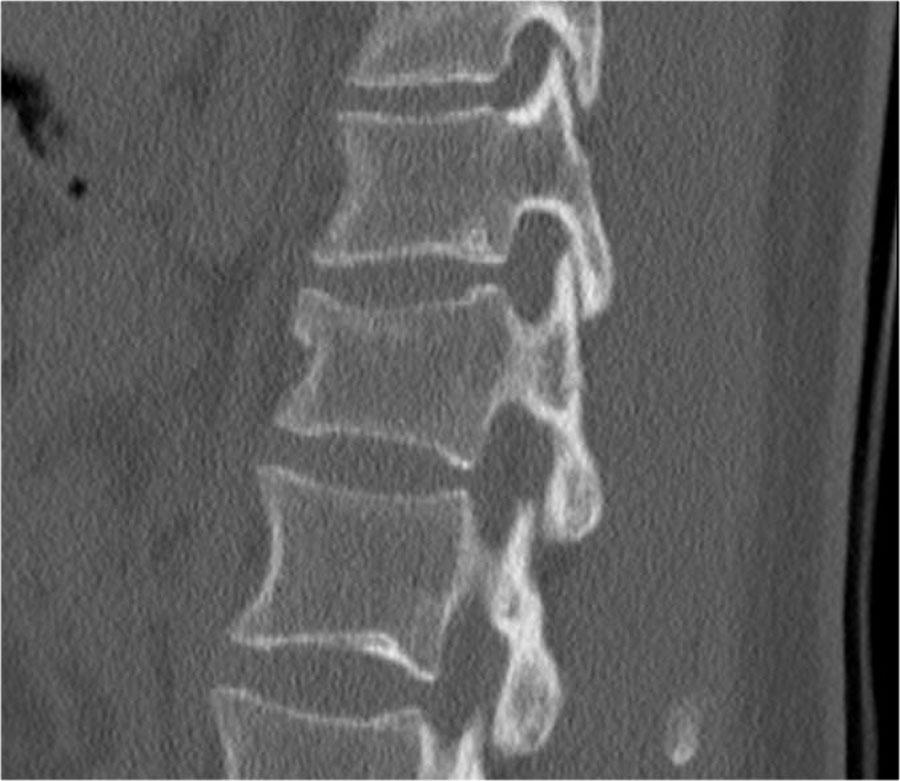

Các hình ảnh là của một bệnh nhân với hình ảnh cột sống tre điển hình do viêm cột sống dính khớp.

Sau khi ngã ngửa, không thấy gãy xương trên phim X-quang.

Tuy nhiên, CT cho thấy một đường gãy mảnh qua mặt trước thân đốt sống và cả qua mỏm gai.

Tiếp tục xem các hình ảnh MRI.